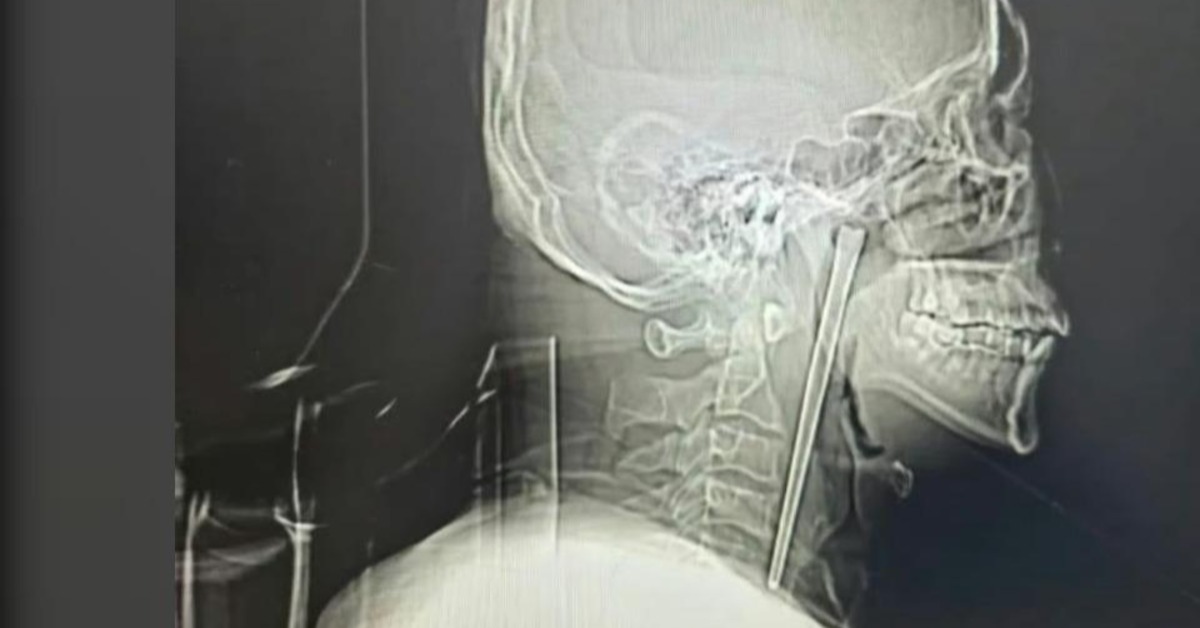

經進一步影像檢查後確認,這個異物正是一根長約12公分的鐵製筷子。醫護人員對此相當震驚,於是進一步詢問其病史。王姓男子才坦承,這根筷子其實是在8年前用餐時不慎誤吞進體內。當時他雖然感覺喉嚨有異物卡住,但因為對手術心存恐懼,始終不願意前往醫院處理。

醫師評估後決定為王姓男子進行微創手術,透過內視鏡技術小心取出異物。手術過程順利,醫療團隊成功將整根金屬筷子完整取出。所幸異物並未對重要組織造成嚴重傷害,術後王姓男子恢復情況良好,喉嚨不適症狀也逐漸改善,日前已康復出院。